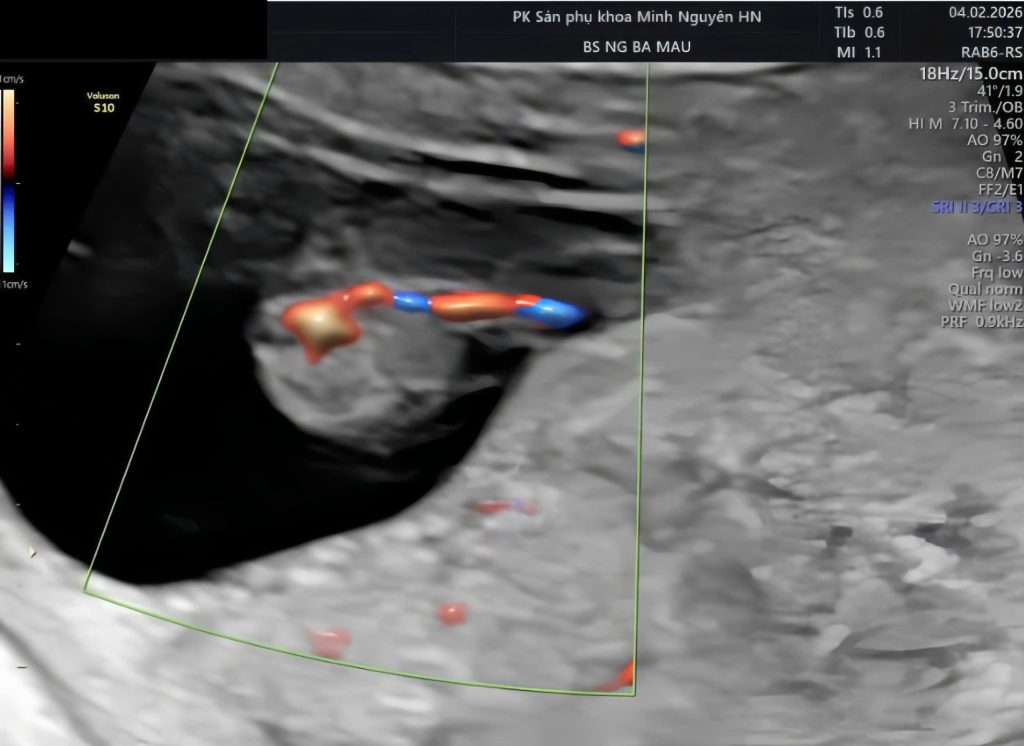

Điều làm chị bế tắc là đọc trên mạng thấy nhiều thông tin trái ngược. Có nơi nói bình thường, có nơi nói liên quan dị tật. Tại phòng khám Dr Tú y học bào thai, việc đầu tiên là đọc lại hồ sơ trong bối cảnh tuổi thai. Sau đó rà lại mặt cắt dây rốn và kiểm tra mạch máu hai bên bàng quang thai để xác nhận chẩn đoán.

Dây rốn một động mạch thường được phát hiện khi siêu âm hình thái giữa thai kỳ. Ở giai đoạn này, mạch máu đủ lớn để quan sát rõ số lượng. Bác sĩ sẽ nhìn mặt cắt ngang dây rốn để đếm số mạch. Đồng thời kiểm tra mạch máu chạy hai bên bàng quang thai.

Nếu chỉ thấy mạch ở một bên bàng quang, đây là dấu hiệu đặc trưng của tình trạng chỉ còn một động mạch rốn. Cách kiểm tra này giúp tăng độ chính xác. Trong một số trường hợp, dây rốn xoắn nhiều hoặc hai động mạch dính đoạn ngắn gần bánh nhau có thể gây nhầm lẫn. Vì vậy, siêu âm kiểm tra lại là bước cần thiết trước khi kết luận.